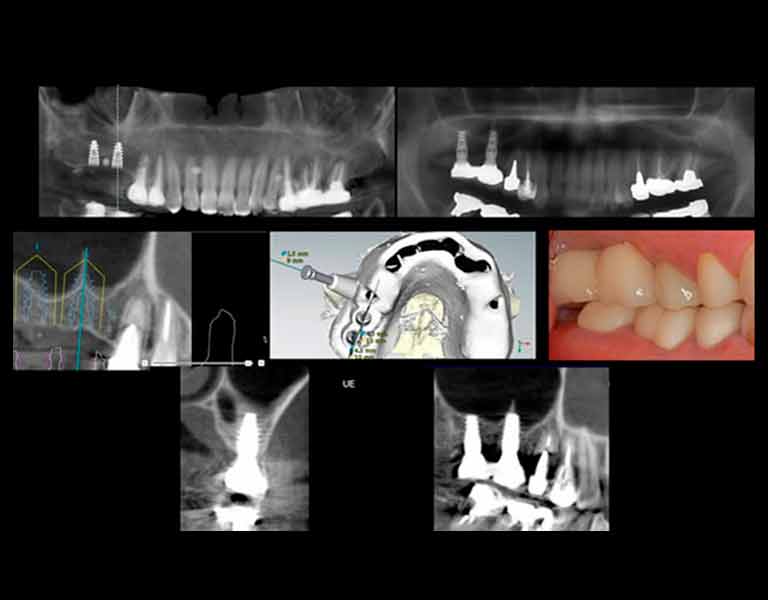

傷口が最小限、スピーディなインプラント手術

フラップレスインプラントとは、従来のインプラント手術とは違って、歯茎を切らずにインプラントを埋め込むことができる技術です。C Tスキャンとコンピュータシミュレーションにより、歯茎を切開せずにインプラント を正確な位置に埋めることができるので、出血や腫れも少なく、早くて安全な手術が可能になります。

歯肉を切らずに手術を行える

ノーベルガイドNobelGuide™システムとは、CTスキャンとコンピュータソフトを使って正確なシミュレーションを行うインプラント手術システムです。従来の治療で必要不可欠だった 切開手術を行わなくても治療が可能なりました。そのため、“より早く・より正確・より安全”なだけでなく、 “より安い”治療が実現したのです。

無駄な手術を回避でき低コスト

インプラント治療での事故は取り返しがつかないこともあります。そんなインプラント治療を担当歯科医の経験と勘だけに任せられますか?例えばタクシーも「ナビゲーションシステム」を装備してより正確でスピーディーなルートを誘導させる時代。インプラント治療にもそんなシステムがあってしかるべきでしょう。インプラント治療のナビゲーションシステムと言えるシステムが「デジタルインプラント」です。